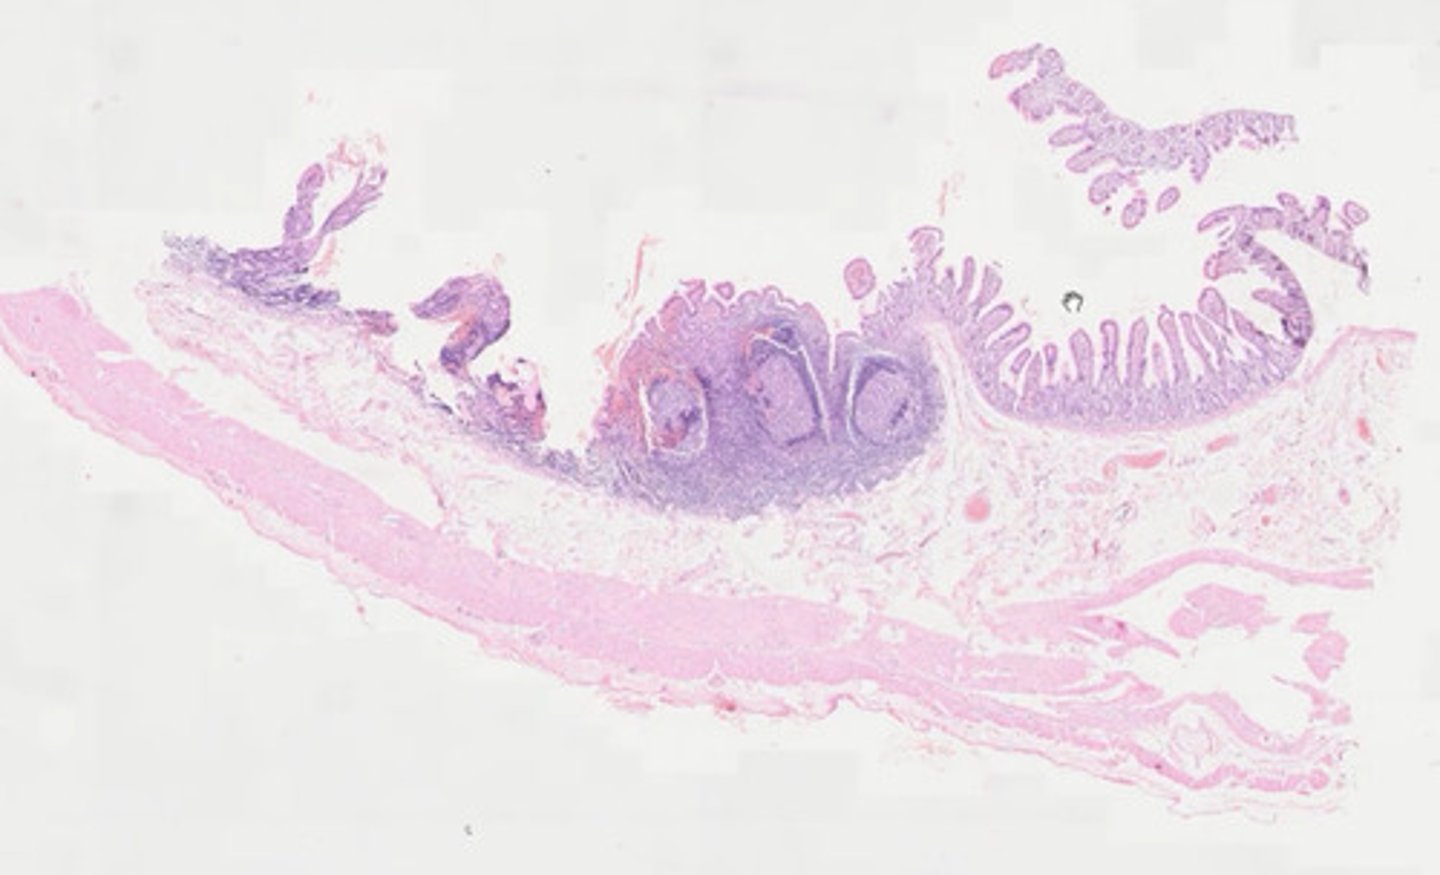

Wyrostek robaczkowy (H+E)